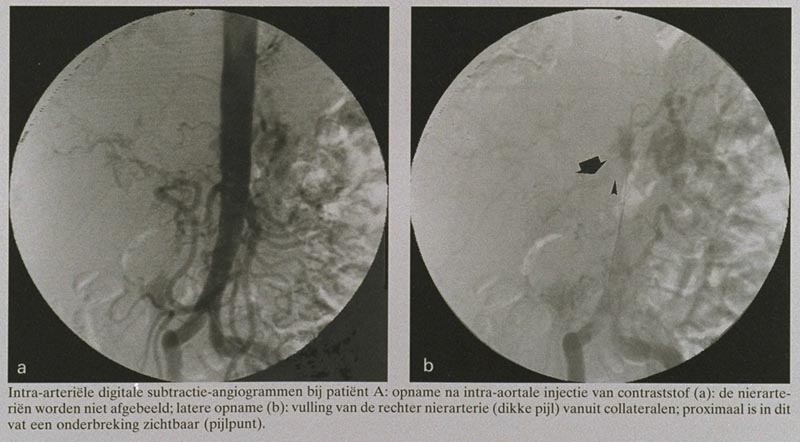

Bij een 61-jarige man bij wie eerder nefrectomie links had plaatsgevonden, en die zich aanmeldde met hypertensie, anurie en recidiverende aanvallen van longoedeem, werd een totale afsluiting van de rechter A. arteria renalis vastgesteld. Dit is een van de manifestaties van ischemische nefropathie, een aandoening die niet zeldzaam is en die tot totaal nierfunctieverlies kan leiden. Om de nierfunctie te verbeteren en chronische dialyse af te wenden dient revascularisatie van de nier(en) verricht te worden, hetzij chirurgisch, hetzij door middel van percutane angioplastiek. Bij de beschreven patiënt werd het stenotische deel van de nierarterie gereseceerd en het vat ‘end to side’ in de aorta gereïmplanteerd, waarna hij goed herstelde.